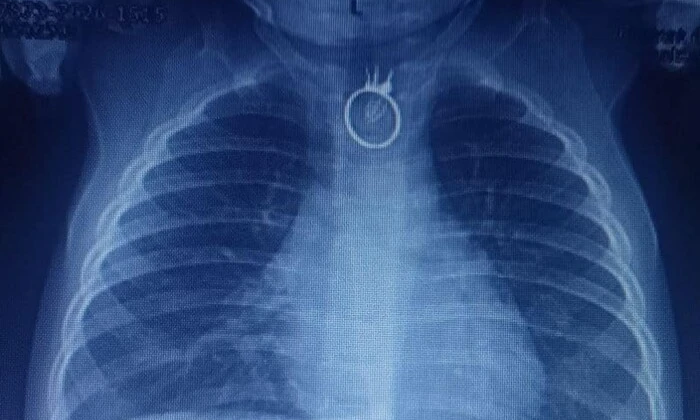

Лікарі Львівської лікарні "Охматдит" врятували 10-місячного хлопчика, який проковтнув іграшковий перстень. Батьки помітили, що син став неспокійним, мав постійну слинотечу, порушення дихання та задишку. Вони зрозуміли, що хлопчик проковтнув сторонній предмет і відразу відправилися до лікарні у Новому Роздолі. Там лікарі зробили рентген, на якому побачили іграшковий перстень. Дитину терміново доставили до Центру дитячої медицини лікарні "Охматдит".